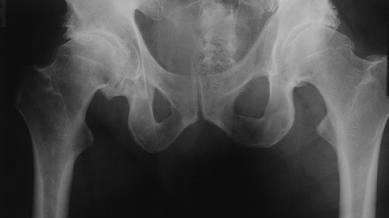

Here's where the problem tends to lie. Humans aren't symmetrical. Different organs are sitting in different places in the abdomen. The liver is on the right, stomach on the left, the intestines are spiralled. Inside the ribcage it's not symmetrical either: the heart mostly sits on the left side, while we have two lobes of the lung on the left and three on the right. All of that and more means that regardless of right- or left-handedness humans have a strong preference for always using the right side of the torso for stability. This means using the right-side postural pattern muscles all the time. Which also means the left-side postural muscles get suppressed.